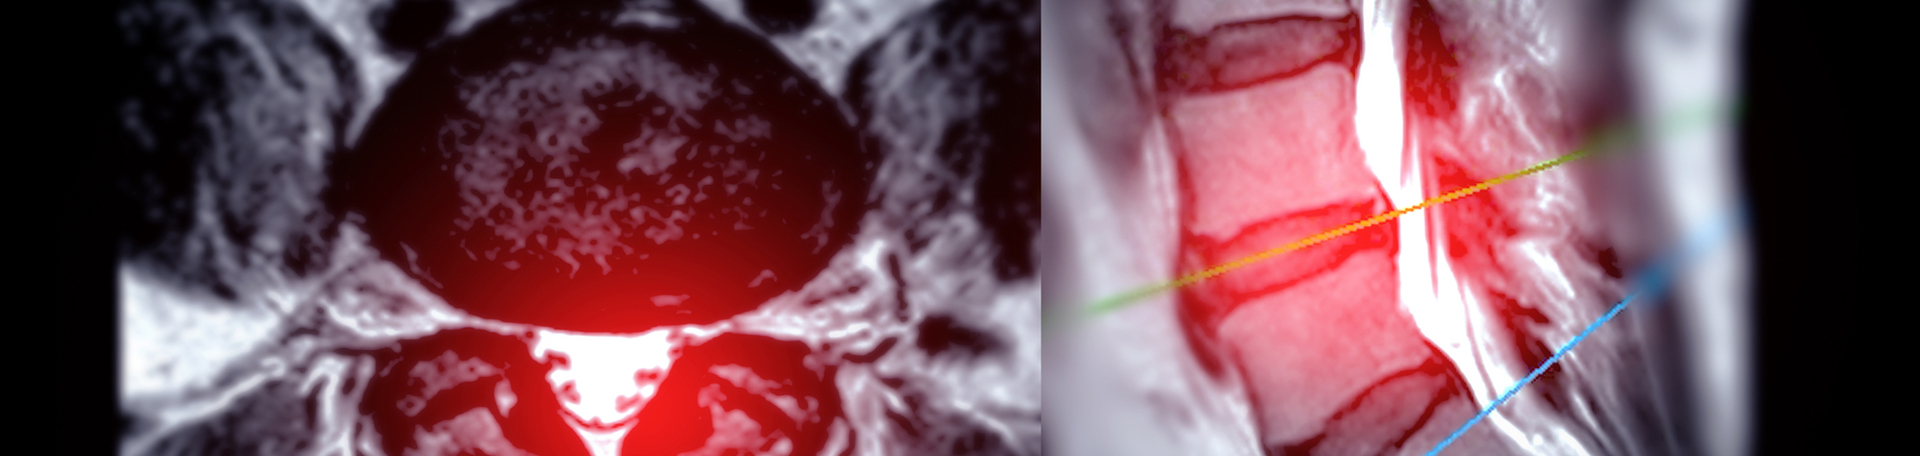

Disc herniation and leg and/or back pain seem to go together, too, but so much more may be incorporated: disc degeneration, ruptured annulus fibrosus, irritation and compression of nerve roots and cauda equina from the herniation itself. A recent study tracked the effects of exercise on a disc herniation’s neuromechanical compression, its inflammatory chemical stimulation, and its autoimmune response. (1) Imaging shows pretty pictures of the disc herniation…that Aurora Chiropractic Center correlates with your symptomatology!

Back pain and imaging seem to go together. When someone experiences back pain, xrays, CTs, and MRIs come to mind. Just what do these demonstrate? A study compared images of symptomatic patients to asymptomatic persons. MR imaging of those with back pain showed that various measurements differed: anteroposterior diameter measures of the vertebral canal varied, transverse diameter was lesser, and thecal sac area was smaller. (2) Caution is warranted in comparing neuroforaminal measurements from CT scans and plain film as a study found that in patients who didn’t have back pain plain film measurements were bigger compared to those on CT. (3) Another imaging finding your Juneau chiropractor is quite aware of is called Modic change. It’s another imaging finding that is quite revealing in that Modic change (mainly type II) is associated with abdominal aortic calcification by way of a lower blood supply or even poorer systemic vascularization due to atherosclerotic disease. (4) It’s another insight we can utilize to determine what is going on in your spine. Finally, a spinal imaging finding that is quite usual in back pain patients is fatty infiltration of the paraspinal muscles, more so in patients with degenerative lumbar spondylolisthesis. (5) We check the MRI images for that though it’s hard to miss! Another good reason to begin a good spinal exercise program!